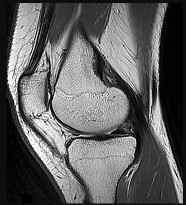

Question 9:

In a varus knee undergoing TKA, a tight medial gap in both flexion and extension indicates a symmetric medial soft tissue contracture. The standard medial release sequence typically begins with the deep medial collateral ligament (MCL) and the posteromedial capsule. If the gap remains tight, further releases may include the superficial MCL (often off the tibia, maintaining the periosteal sleeve) and the pes anserinus. Releasing the lateral structures (LCL, IT band, popliteus) would worsen the varus imbalance.